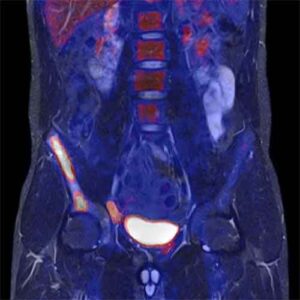

A Napoli nuovo macchinario diagnostico per eseguire 'in un colpo' risonanza magnetica e Pet. La Fondazione Sdn di Napoli, infatti,...